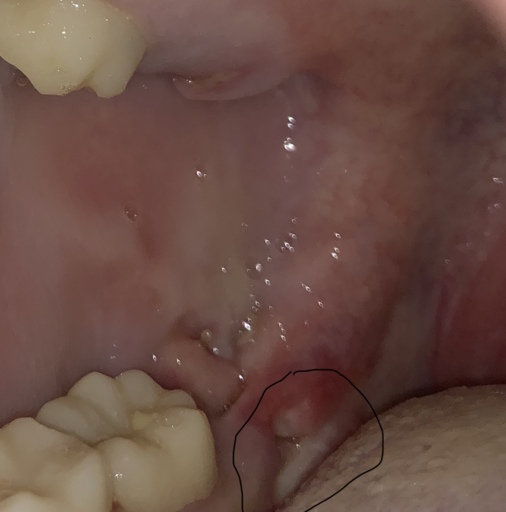

Do I need a biopsy? Is this a mucucele?

See pics please. This is soft to the touch. Been there a few years. I thought is was a blocked saliva duct but now it has the dark area beneath it which is new. Of note. About 6 years ago a general dentist said to keep an eye on it for any...